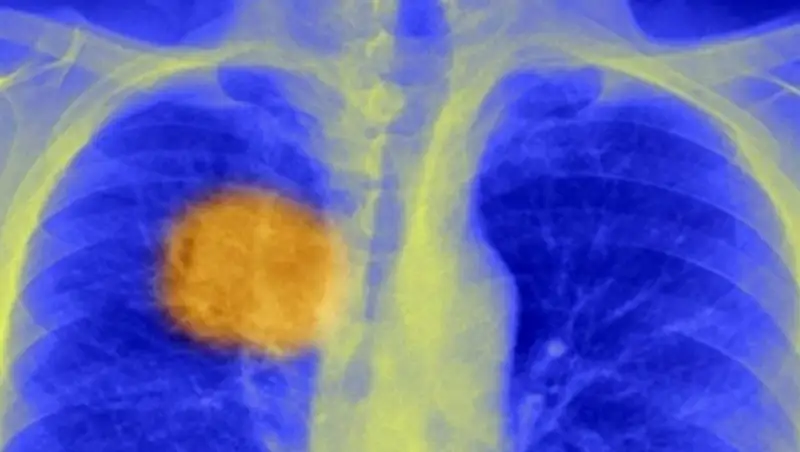

Зарубежные ученые провели исследования, которые показали, что большая доза дофамина может стимулировать мозговую активность. По мнению специалистов из Йельской медицинской школы в Нью-Хейвене, вводить ее нужно при помощи инъекций.

Дофамин, считают эксперты, поможет избавиться от последствий болезни Паркинсона. В рамках исследования была выявлена прямая зависимость между уровнем дофамина и активностью гена 1 (HAR1).

Сейчас ученые заявляют, что дальнейшие клинические опыты могут привести к тому, что медики впервые получат возможность не только ликвидировать последствия недугов, но и улучшать умственные способности человека через инъекции.